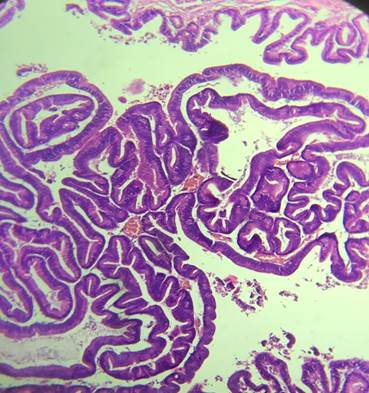

La anatomía patológica de la pieza quirúrgica informa neoplasia papilar intraductal de vía biliar, con displasia epitelial de bajo grado, sin infiltración del estroma (in situ), lesión temprana. (Fig.3,4).

Fig. 3 y 4: Informe anatomopatológico: examen macroscópico parénquima hepático que se recibe previamente seccionado de 12,5 x 3 cm. Examen microscópico: los cortes histológicos muestran parénquima hepático en el que se reconoce estructura ductal marcadamente con formaciones papilares en su interior con eje conectivo vascular revestidas por epitelio cilíndricos de núcleos alongados e hipercrómicos, en sectores con estratificación nuclear, cromatina granular y nucléolos evidentes.